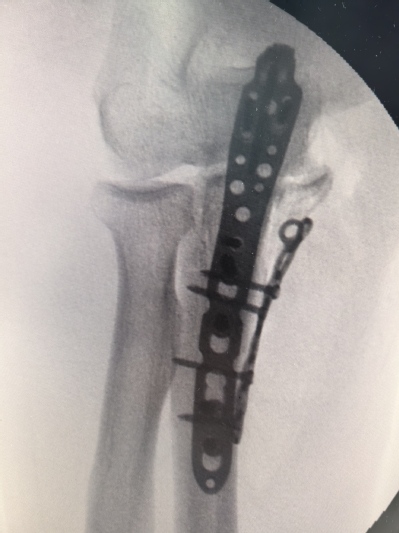

一名69岁男性,因不慎撞伤导致肘关节明显肿胀疼痛,不能活动,当即来金沙娱乐城app 就诊。行x线检查后示尺骨近段粉碎性骨折。经过吴卫东、黄晟医生仔细读片后诊断为经尺骨鹰嘴孟氏骨折。骨折断裂情况严重,尺骨鹰嘴、尺骨冠突骨块分离,同时存在肘关节内侧不稳定,病情复杂,手术难度非常大。

此次手术,借助先进3D打印技术,精确复制了患者骨折部位的骨骼结构,为手术提供了直观、详尽的参考。经过吴卫东、黄晟手术团队的努力,患者的粉碎性骨折得到了有效治疗,术后恢复良好。